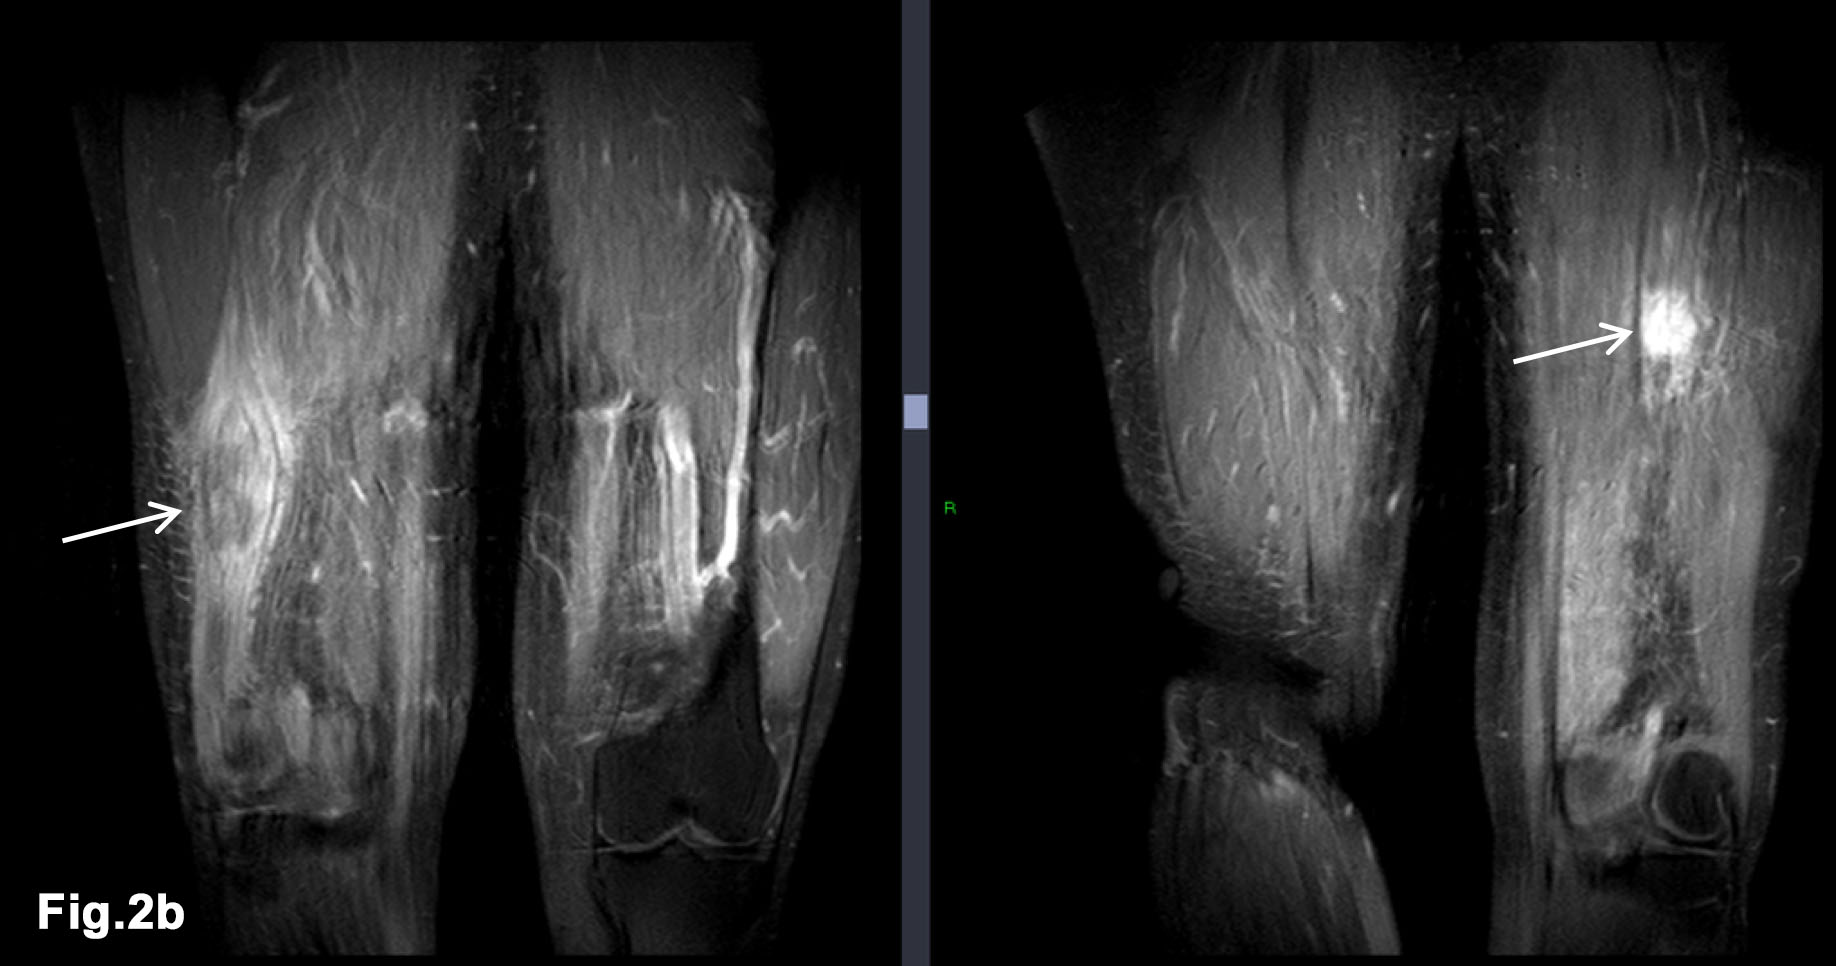

Figure 2 – initial external MR - confirms larger mass within right distal biceps femoris muscle (solid arrow) and demonstrates further, smaller mass between fat plans of left posterior thigh muscles (line arrow) - T1w and PDW DRI images (Fig 2a) - T1W FS Gadolinium enhanced MR – demonstrates enhancing intramuscular lesions with peripheral oedema (arrows) (Fig 2b)

- There was an abnormal soft tissue mass in the distal posterior thigh, related to the biceps femoris.

- MRI 2016 (Figure 2)

- Elliptical mass like lesion measuring 7.2 x 2.7cm on T1 weighted imaging which was isointense to normal muscle but demonstrates patchy, peripheral enhancement following gadolinium injection. The mass was within the short head of biceps femoris muscle.

- Another smaller similar lesion was noted within left thigh, measuring 2.9cm lying in the fat plane between posterior thigh muscles.